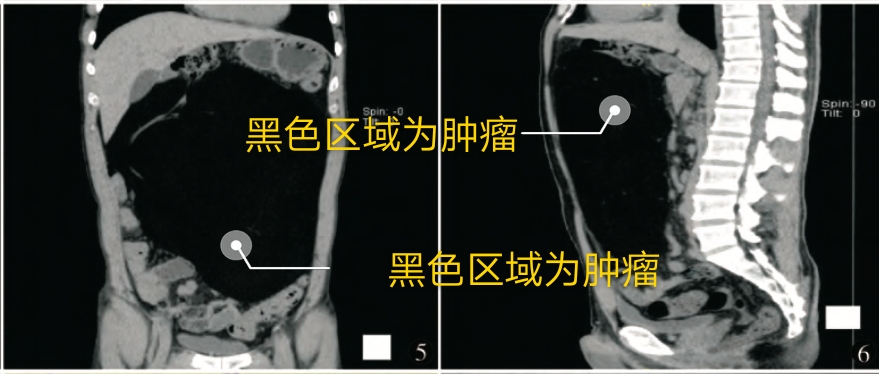

冠状位,矢状位观察,肿瘤几乎占满腹盆腔,将肠管挤向边缘

腹腔盆腔可见巨大肿块,占满腹盆腔,病灶呈脂质低密度,其密度不均,增强后无明显强化,肝脏受压,肝门部变形,胰腺受压变形。肿瘤体积约32×22×15cm。考虑为脂肪肉瘤。